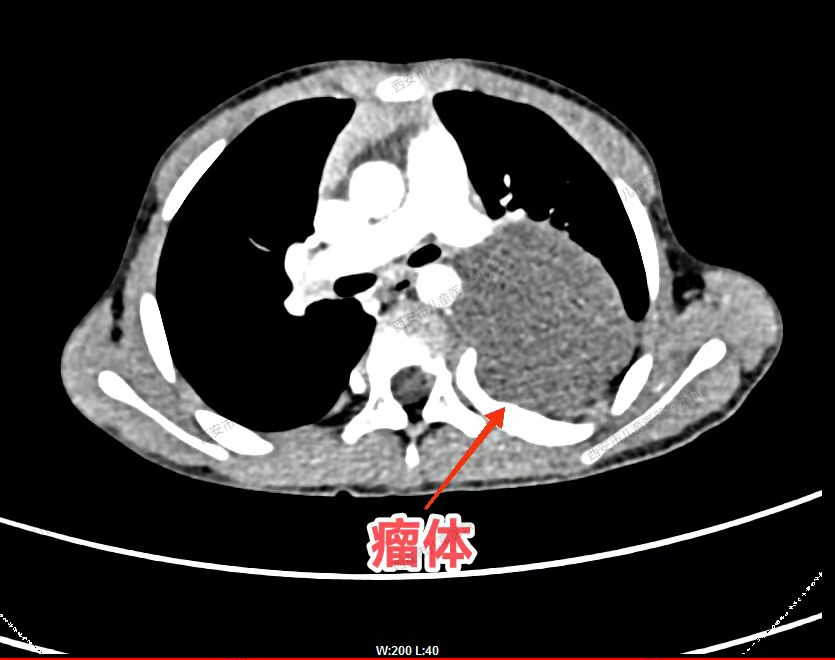

患者,女性,73岁,咳嗽,咳痰10余天,在当地医院行平扫诊断为纵膈肿瘤